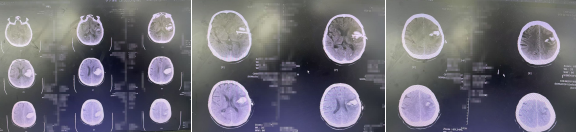

血肿穿刺(微创)